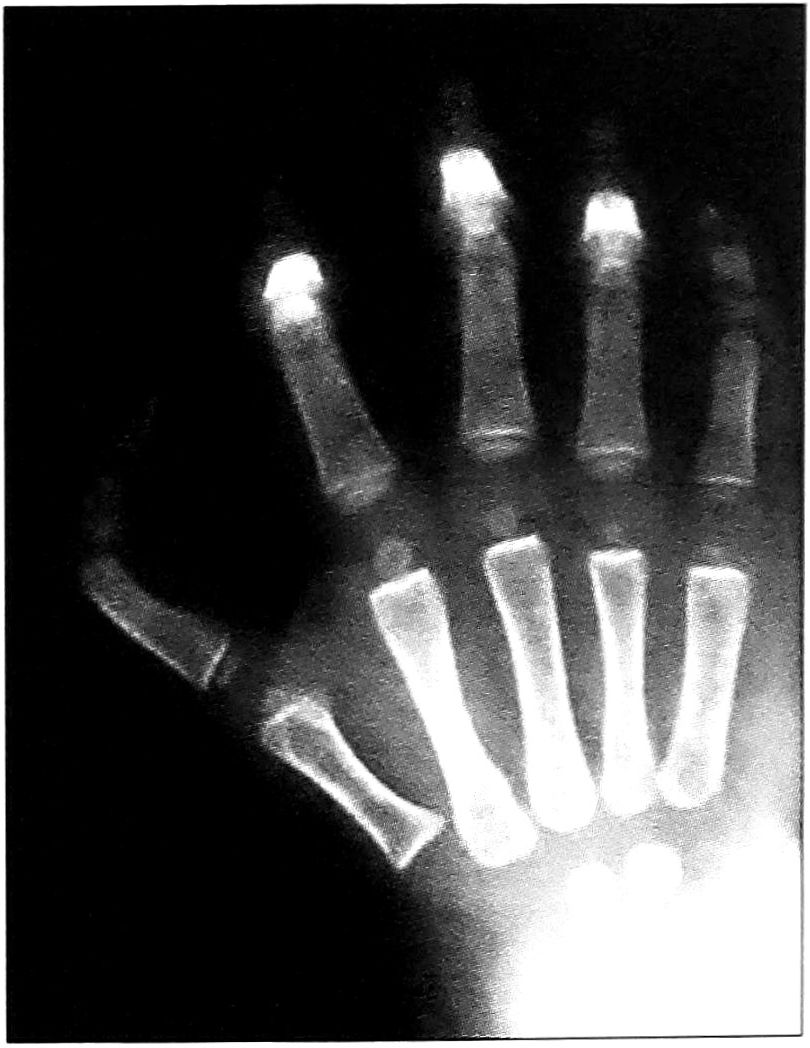

- Брахимезофалангеальная форма врожденного трехфалангизма I пальца кисти (рис. 1). Характеризуется следующими признаками:

- продольные размеры I пястной кости соответствуют норме или незначительно увеличены (увеличение состаляет до 10%), поперечные размеры также соответствуют норме либо отмечается незначительная поперечная гипо/гиперплазия (до 10%);

- эпифиз I пястной кости чаще расположен проксимально, однако возможно дистальное его расположение (так называемый псевдоэпифиз) или удвоение эпифиза (проксимальный и дистальный) по мере увеличения размеров средней фаланги;

- дополнительная фаланга по размерам меньше или равна дистальной фаланге, ее форма треугольная, трапециевидная либо прямоугольная;

- продольные размеры I луча кисти увеличены до 20% от возрастной нормы;

- величина первого межпястного промежутка нормальная либо умеренно уменьшена (не более чем на 10°).

Рис. 1. Варианты брахимезофалангеальной формы трехфалангизма.

По мере перехода от треугольной средней фаланги к трапециевидной, от трапециевидной к прямоугольной в тератологическом ряду брахимезофалангеальной формы трехфалангизма изменяются следующие параметры:

- уменьшается поперечный и увеличивается продольный размер I пястной кости (формируется поперечная гипоплазия и продольная гиперплазия);

- происходит формирование псевдоэпифиза или удвоение эпифиза I пястной кости;

- увеличиваются размеры основной и средней фаланг, уменьшаются — дистальной;

- появляется зона роста средней фаланги;

- формируются два межфаланговых сустава — проксимальный и дистальный;

- уменьшается первый межпястный промежуток;

- увеличиваются продольные размеры I луча кисти.